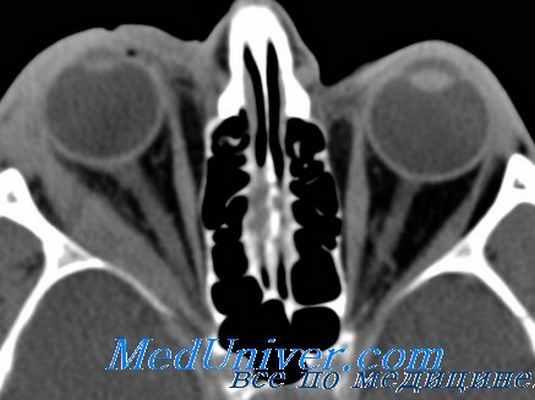

В диагностике абсцесса глазницы и его осложнений у всех использованы лучевые методы исследования орбит, придаточных пазух носа, головного мозга: обзорная рентгенография (РУМ–20, Se 16,7%); мультиспиральная компьютерная томография — МСКТ (LightSpeed 16 GE, Se 88,9%) и магнитно-резонансная ангиография (Signa Excite (1,5T) GE). Чувствительность (Se) лучевых методов оценивалась на выявлении экссудативной отслойки периоста, верифицированной во время операции.

При рентгенографии орбит и придаточных пазух носа обнаружено затемнение верхнечелюстной пазухи (рис. 2г). При МСКТ выявлены: экссудат в пазухах носа, деструкция нижней стенки орбиты, экссудативная отслойка периоста, верифицированные во время операции, что позволило подтвердить контактный путь инфицирования орбиты. У 2 больных с хроническим гайморитом контузионная травма способствовала прямому пути инфицирования орбиты через трещину костной стенки (рис. 3). У 5 (38,5%) из 13 пациентов отмечалось осложненное течение субпериостального абсцесса с молниеносным развитием тромбофлебита вен лица и крылонебной ямки, тромбоза кавернозного синуса (4) на фоне сепсиса. При магнитно-резонансной ангиографии выявлено расширение верхней глазной вены, затруднение венозного оттока (рис. 4), что подтвердило гематогенный путь инфицирования орбиты из полости рта по лицевой, угловой венам и по венам крылонебной ямки через нижнюю глазничную щель. Осложненное течение СПА наблюдали на фоне сахарного диабета, туберкулеза легких, гепатита В. В экссудате орбиты выявлены ассоциации грамотрицательных микроорганизмов (Klebsiella, E. coli); аэробов и анаэробов (Staph. аureus, Strept. viridans, Enterococcus faecium), резистентных к антибиотикам, аналогичные микрофлоре полости рта. У 4 пациентов с сепсисом в крови обнаружены устойчивые к антибиотикам E. coli (2), Staph. aureus (2).

Для диагностики применяют стандартные методы: визометрию, биомикроскопию, тонометрию, периметрию. Для точного определения локализации субпериостального абсцесса орбиты дополнительно используют лучевые методики. Рентгенография орбит и придаточных пазух носа в прямой и боковой проекциях позволяет диагностировать куполообразную (экссудативную) отслойку надкостницы орбиты и увеличение денситометрической плотности клетчатки глазницы вокруг очага воспаления.

Ультразвуковое исследование глаза и орбиты выявляет изменение размера ретробульбарного пространства, хода экстраокулярных мышц. КТ или МРТ орбит, придаточных пазух носа и головного мозга помогает определить отслойку периоста в зоне поражения. Кроме того, при субпериостальном абсцессе орбиты требуется консультация отоларинголога, челюстно-лицевого хирурга и нейрохирурга. Проводится бактериальный посев гнойного отделяемого с определением чувствительности к антибактериальным препаратам.